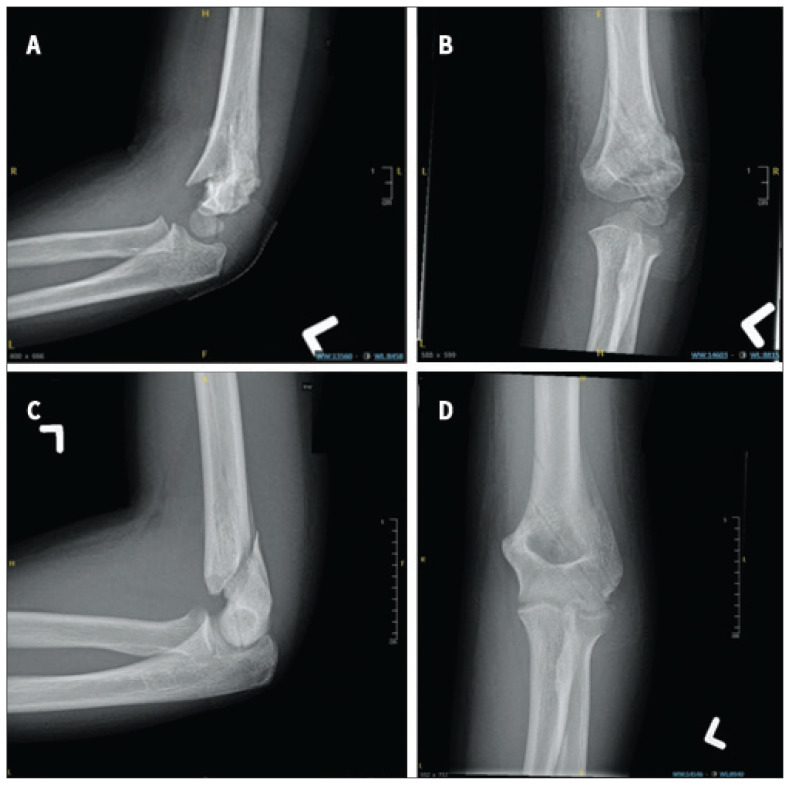

Background: Use of postoperative radiographs after surgical management of supracondylar humerus (SCH) fractures is often based on rote practice rather than evidence. The purpose of this study was to determine the frequency with which 3-week postoperative radiographs at the time of pin removal altered management plans in pediatric SCH fractures that were intraoperatively stable after closed reduction and percutaneous pinning (CRPP).

Methods: We prospectively recruited pediatric patients with SCH fractures managed by CRPP at our institution from June 2020 until June 2022, and reviewed retrospective data on pediatric SCH fractures managed surgically at our institution between April 2008 and March 2015. Patients were assessed for post-CRPP fracture alignment and stability. For prospective patients, we asked clinicians to document their management decision at the 3-week follow-up visit before evaluating the postoperative radiographs. Our primary outcome was change in management because of radiographic findings.

Results: Overall, 1066 patients in the retrospective data and 446 prospectively recruited patients met the inclusion criteria. In the prospective group, radiographic findings altered management for 2 patients (0.4%). One patient had slow callus formation and 1 patient was identified as having cubitus varus. Altered management included prolonged immobilization or additional radiographic follow-up. Radiographic findings altered management in 0 (0%) of 175 type II fractures, in 2 (0.9%) of 221 type III fractures, and in 0 (0%) of 44 type IV fractures. We obtained similar findings from retrospective data.

Conclusion: Rote use of 3-week postoperative radiographs after surgical management of SCH fractures that are intraoperatively stable has minimal utility. Eliminating rote postoperative radiographs for SCH fractures can decrease the time and financial burdens on families and health care systems without affecting patient outcomes.